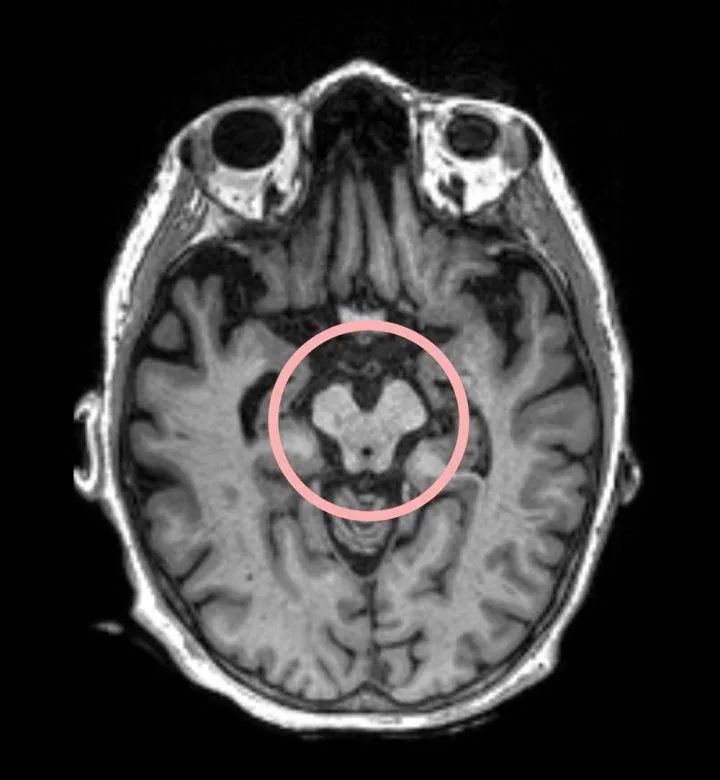

脑部扫描显示红色圆圈区域存在进行性核上性麻痹